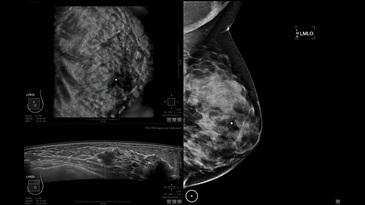

GE INVENIA ABUS – это современный УЗИ аппарат, который создан для точной и эффективной диагностики сканирования с высокой плотностью молочных желез. Выявляемость патологий раковых и предраковых стадий заболевания составляет 55%, что в конечном счете позволяет ставить врачу точные и своевременные диагнозы. Традиционные методы использования маммографии не показывают такой выявляемости, ограничиваясь лишь 3-38%.

УЗИ-аппарат GE INVENIA ABUS позволяет проводить максимально операторонезависимые процедуры, что значительно снижает риск неправильной постановки диагноза и сопутствующие издержки на обработку информации. Система готовит отчет в течение 3-х минут после сканирования, это безусловное преимущество по сравнению с обычным УЗИ сканером.

• датчик с изогнутой апертурой для качественного исследования

• сканирование одной грудной железы в трех проекциях не более 60 сек.;

• обработка результатов за три минуты.

Возможности встроенной УЗ-системы:

• Увеличение или уменьшение степени сжатия грудной железы;

• Функция автоматического сканирования активируется одним нажатием;

• Возможность отмены сканирования;

• Глубина проникновения УЗ-лучей – до 50 мм;

• Одно детализированное изображение можно получить менее чем за 1 минуту

• Многорядная светодиодная подсветка;

• Встроенный сверхширокий вогнутый датчик С15-6ХW.